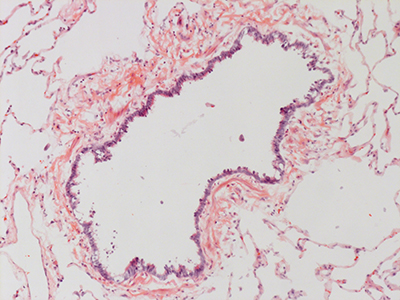

31 Year Old Adult Human Lung DD037 H&E